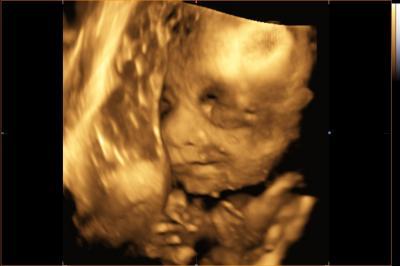

Hallo ihr Lieben! Jetzt habe ich mich mal drei Wochen ausgeklingt und wollte mich mal wieder melden. Meine Mama war zu Besuch (wohnt sonst in den USA) und wir haben die Zeit sehr genossen mit Weihnachtsmärkten, Nähen, Babykataloge wälzen und gemütlichen Kaminabenden. Ich bin jetzt also höchstentspannt und muss auch nur noch eine Woche arbeiten in diesem Jahr! Unserer Püppi geht es ebenfalls bestens, wir durften heute morgen wieder gucken und diesmal konnten wir die Kleine sogar ohne Hand vor dem Gesicht erwischen. Ca. 730 Gramm hat sie, die Größe ließ sich schwer schätzen, hat zuviel gezappelt. Auch mein Bauch wächst und mittlerweile hat es dann auch der letzte Arbeitskollege mitbekommen... Bin schon ganz gespannt, was bei euch so in der letzten Zeit passiert ist und werde mich gleich mal durch die Beiträge kämpfen. Wünsche euch einen schönen Tag! Ach ja, ab morgen: Drittes Trimester!!

Schön das es dir und deiner Püppi so gut geht. Das Bild is toll, sie lächelt ja wie süß; ). Lg

das klingt wirklich nach einer sehr entspannten zeit mit deiner mama! toll! mensch 730g das ist ja der wahnsinn. die kleinen legen jetzt echt heftig zu. das bild ist ja wirklich sehr gelungen! unsere maus hat am liebsten die plazenta oder eine hand vorm gesicht :o)

Wie süß - ein Lächeln!